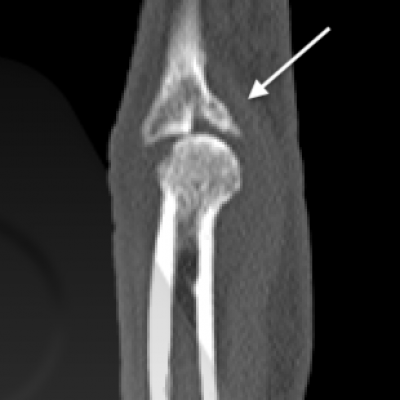

- Cartilage – Fractures that extend into the joint can injure the smooth cartilage surfaces that cover the bone ends that form the moving parts of the joint. These injuries can lead to a long term risk of arthritis in some cases.